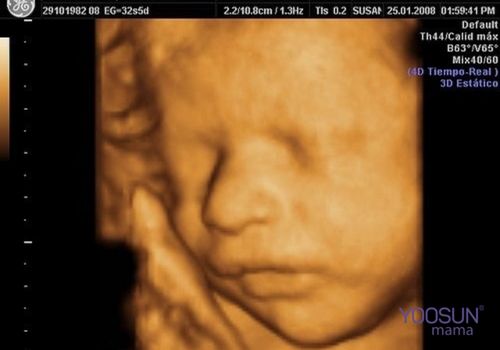

Siêu âm 4D hay còn có tên gọi khác là siêu âm 4 chiều. Siêu âm cho kết quả 3 chiều không gian và 1 chiều thời gian. Kỹ thuật siêu âm thai 4D giúp cung cấp các hình ảnh chuyển động thực tế của thai nhi ngay tại thời điểm siêu âm.

Thông qua màn hình máy tính cha mẹ, bác sĩ sẽ thấy được những cử chỉ của thai nhi như: Giơ tay, đạp chân, xoay mình, ngáp ngủ… Một số trường hợp siêu âm còn thấy em bé đang mút tay…

Siêu âm 4D, cấu trúc bên trong cơ thể không chỉ được thể hiện bằng hình ảnh màu mà còn cho thấy các chuyển động giống như thước phim. Hình ảnh siêu âm thai 4D chân thực hơn.